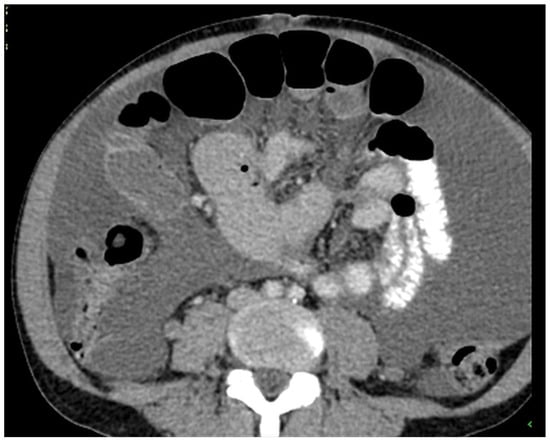

Figure 3. Another example of an appendiceal mucocele with calcification in the wall (arrow) (CT, venous phase, axial plane).